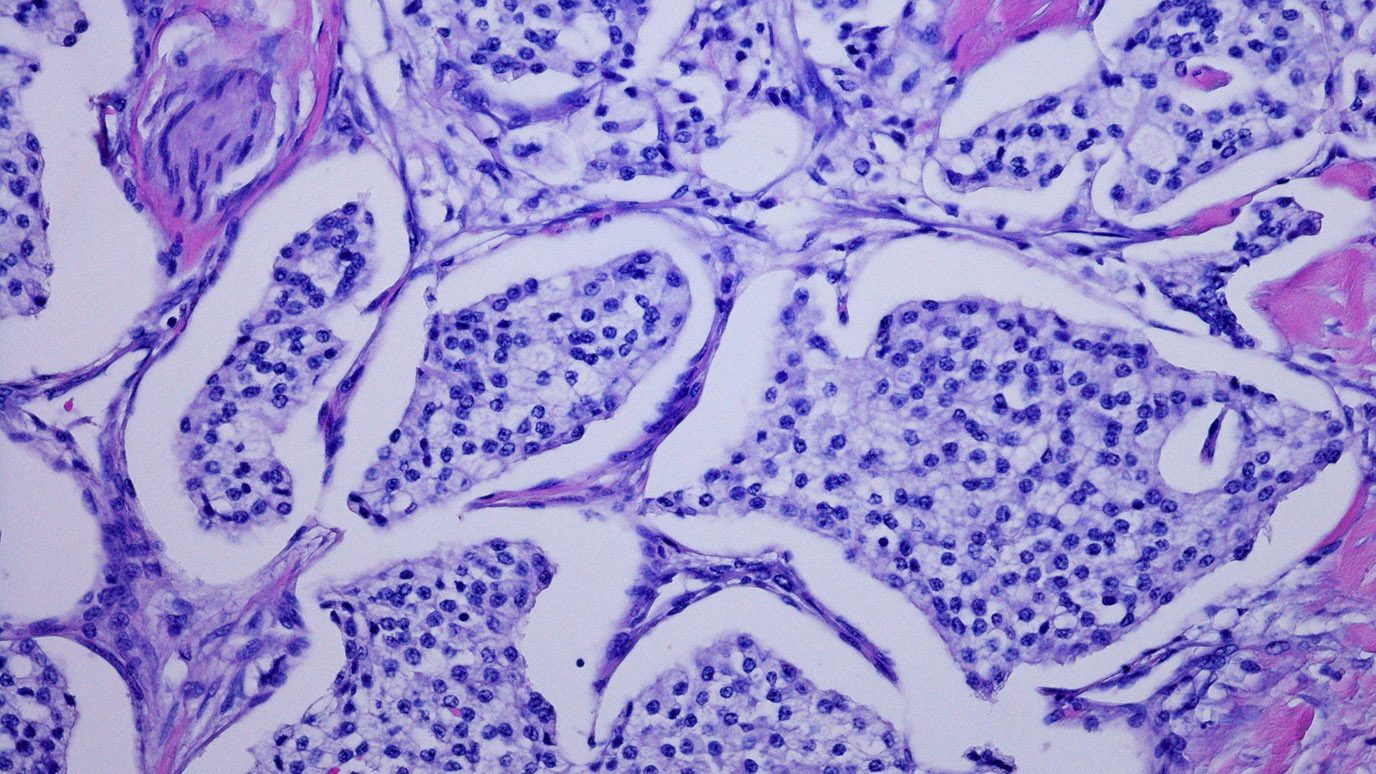

Combination immunotherapy with the anti-PD-L1 monoclonal antibody durvalumab and other novel agents outperforms durvalumab alone in the neoadjuvant (pre-surgical) setting for early-stage non-small-cell lung cancer (NSCLC), according to researchers from The University of Texas MD Anderson Cancer Center.

The findings, published today in Cancer Discovery, were first presented at the American Association for Cancer Research...